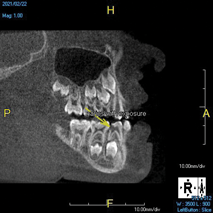

The idea that a dentist may be incorrect in his or her diagnosis is distasteful, but a reality that this profession wrestles with on a daily basis. An image comparison can help to clarify this thought. The first image is a 2D radiograph of tooth No. 19 that includes the buccal cortical plate the lingual cortical plate and approximately 10 mm of trabecular bone compressed into a single image (Figure 1). Because the full width and volume of the tooth is included in the image, any existing pathoses could be masked or hidden in a fog of digital information. A CBCT scan of the same tooth provides more detail because it can present a slice (0.1 mm) of information from the center of the area in question (Figure 2). All of the extraneous information is eliminated, and the clinician and the patient have a more precise picture to evaluate. Furthermore, a periapical radiograph can be distorted by the angle of the cone to the sensor, whereas a CBCT scan has no distortion and is accurate in all views. With a CBCT scan, the clinician is able to state with certainty that a condition exists, and the patient is able to more clearly understand what his or her condition is when considering the available choices for treatment.

(2.) Two-dimensional periapical radiograph of tooth No. 19 compared with a CBCT scan slice (0.1 mm) of the same tooth, which reveals a well-defined lesion that a patient can more easily understand.

Figure 2

(8.) An original finding of a small lesion on the mesial root of tooth No. 30 was not accompanied by any outward symptoms; therefore, the patient delayed pursuing treatment. When a follow-up CBCT scan was acquired 6 years later, the easy-to-visualize increase in the dimensions of the lesion motivated the patient to elect a treatment plan.

Figure 8

(9.) An original finding of a small lesion on the mesial root of tooth No. 30 was not accompanied by any outward symptoms; therefore, the patient delayed pursuing treatment. When a follow-up CBCT scan was acquired 6 years later, the easy-to-visualize increase in the dimensions of the lesion motivated the patient to elect a treatment plan.

Figure 9